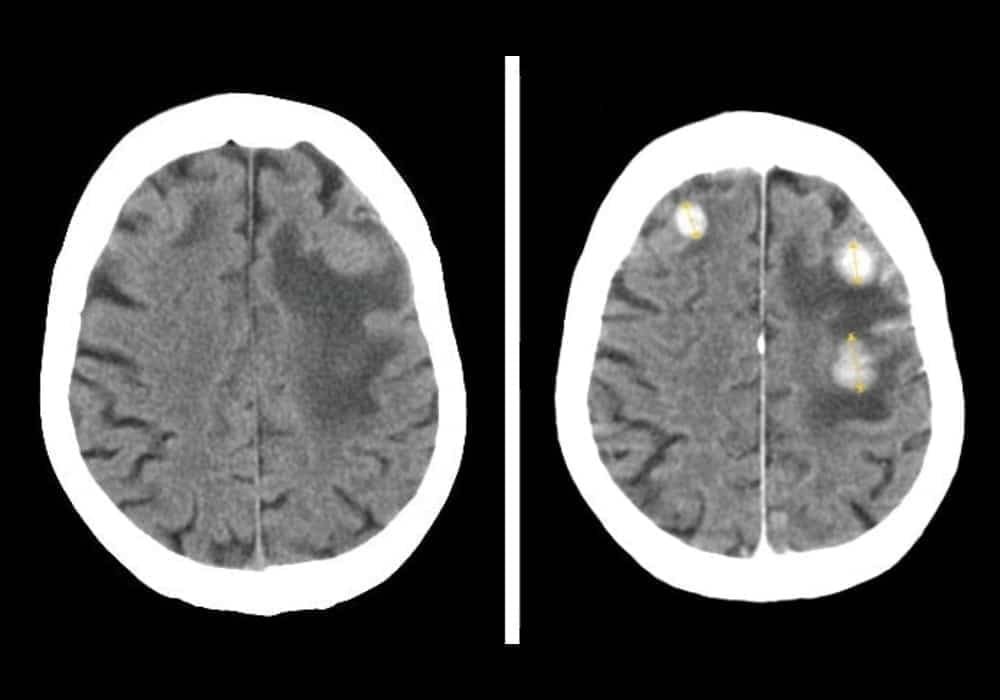

Sumber foto: Wikimedia